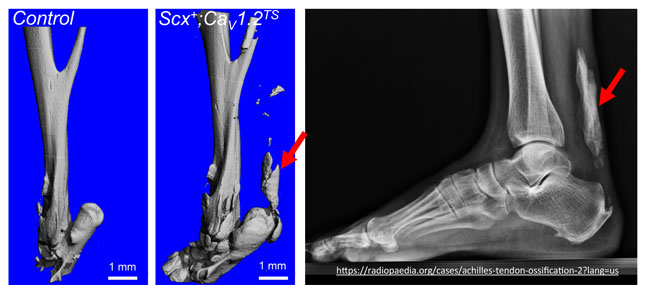

HO is an ectopic and pathological bone formation in extraskeletal tissues, including skeletal muscle, fascia, tendons and ligaments and can be induced by traumatic injury or in patients with genetic disorders. HO causes pain and reduces range of motion that progresses to immobilization and devastates health and daily life. No treatment is currently available and the precise pathophysiology of HO remains unknown. Therefore, better understanding of the cellular and molecular mechanisms that underlie the dysregulated mesenchymal progenitor cell commitment and of the signaling pathways involved in the disease processes is in need to identify therapeutic strategies that can prevent HO initiation and/or progression. Our laboratory has established a new HO mouse model, by which activating CaV1.2-TS mutant channel expression in tendon lineage cells induces Achilles tendon ectopic bone formation at 8 weeks old. It progresses more severe as age in the absence of injury. Notably, we have previously demonstrated that CaV1.2 is expressed in osteoprogenitor cells and increased Ca2+ influx via CaV1.2 has great osteogenic potential in both in vivo mouse models and in vitro BMSC culture system. Pharmacological approaches and allele ablation further demonstrated that Ca2+ influx via CaV1.2 channel is necessary for BMSC osteogenesis in culture. In this project, we aim to understand the role of Ca2+ signaling pathways via CaV1.2 and their cross-talk with other signaling pathways in mesenchymal cell fate determination during HO formation.

HO photo